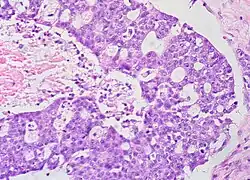

Mucinous

Mucinous tumors include mucinous adenocarcinoma and mucinous cystadenocarcinoma.[29]

Mucinous adenocarcinoma

Mucinous adenocarcinomas make up 5–10% of epithelial ovarian cancers. Histologically, they are similar to intestinal or cervical adenocarcinomas and are often actually metastases of appendiceal or colon cancers. Advanced mucinous adenocarcinomas have a poor prognosis, generally worse than serous tumors, and are often resistant to platinum chemotherapy, though they are rare.[29]